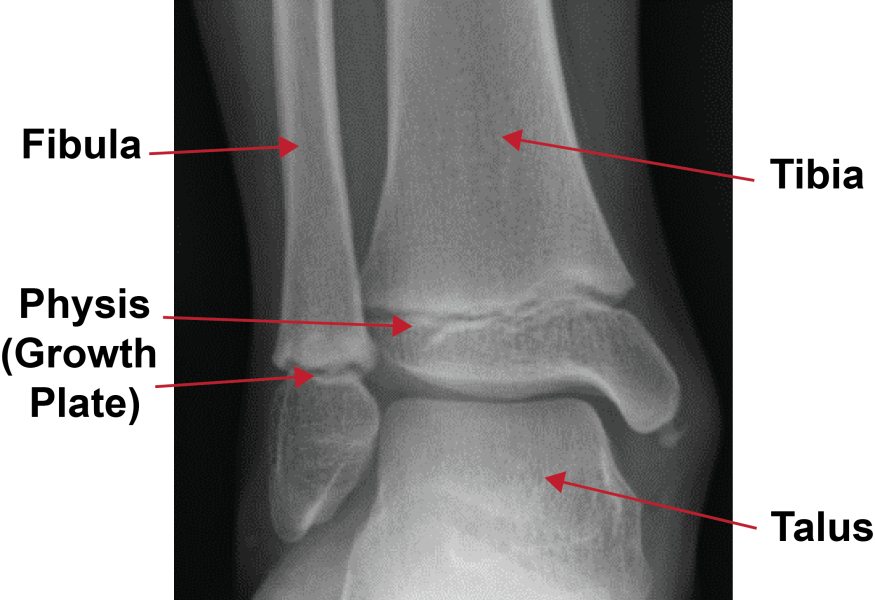

The ankle is made up of three bones: the tibia (shin bone), the fibula (calf bone) and the talus (part of the ankle joint). In children and teens, an ankle fracture can damage the growth plates at the end of each leg bone. Any growth plate fracture can have long-term effects. It is important to see a doctor quickly.

An X-ray is the most common way to look at an ankle fracture. The physician also looks at the growth plates to check for injury.

The arrows on this X-ray show the growth plate fractures.